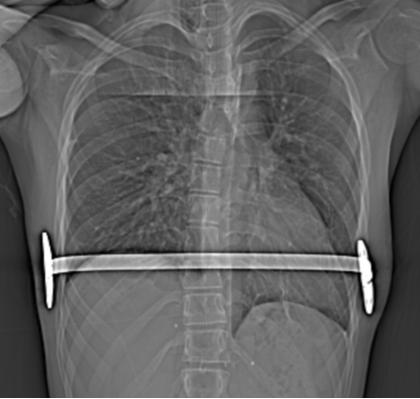

术后的胸片显示置入的钢板位置良好,胸廓矫形满意